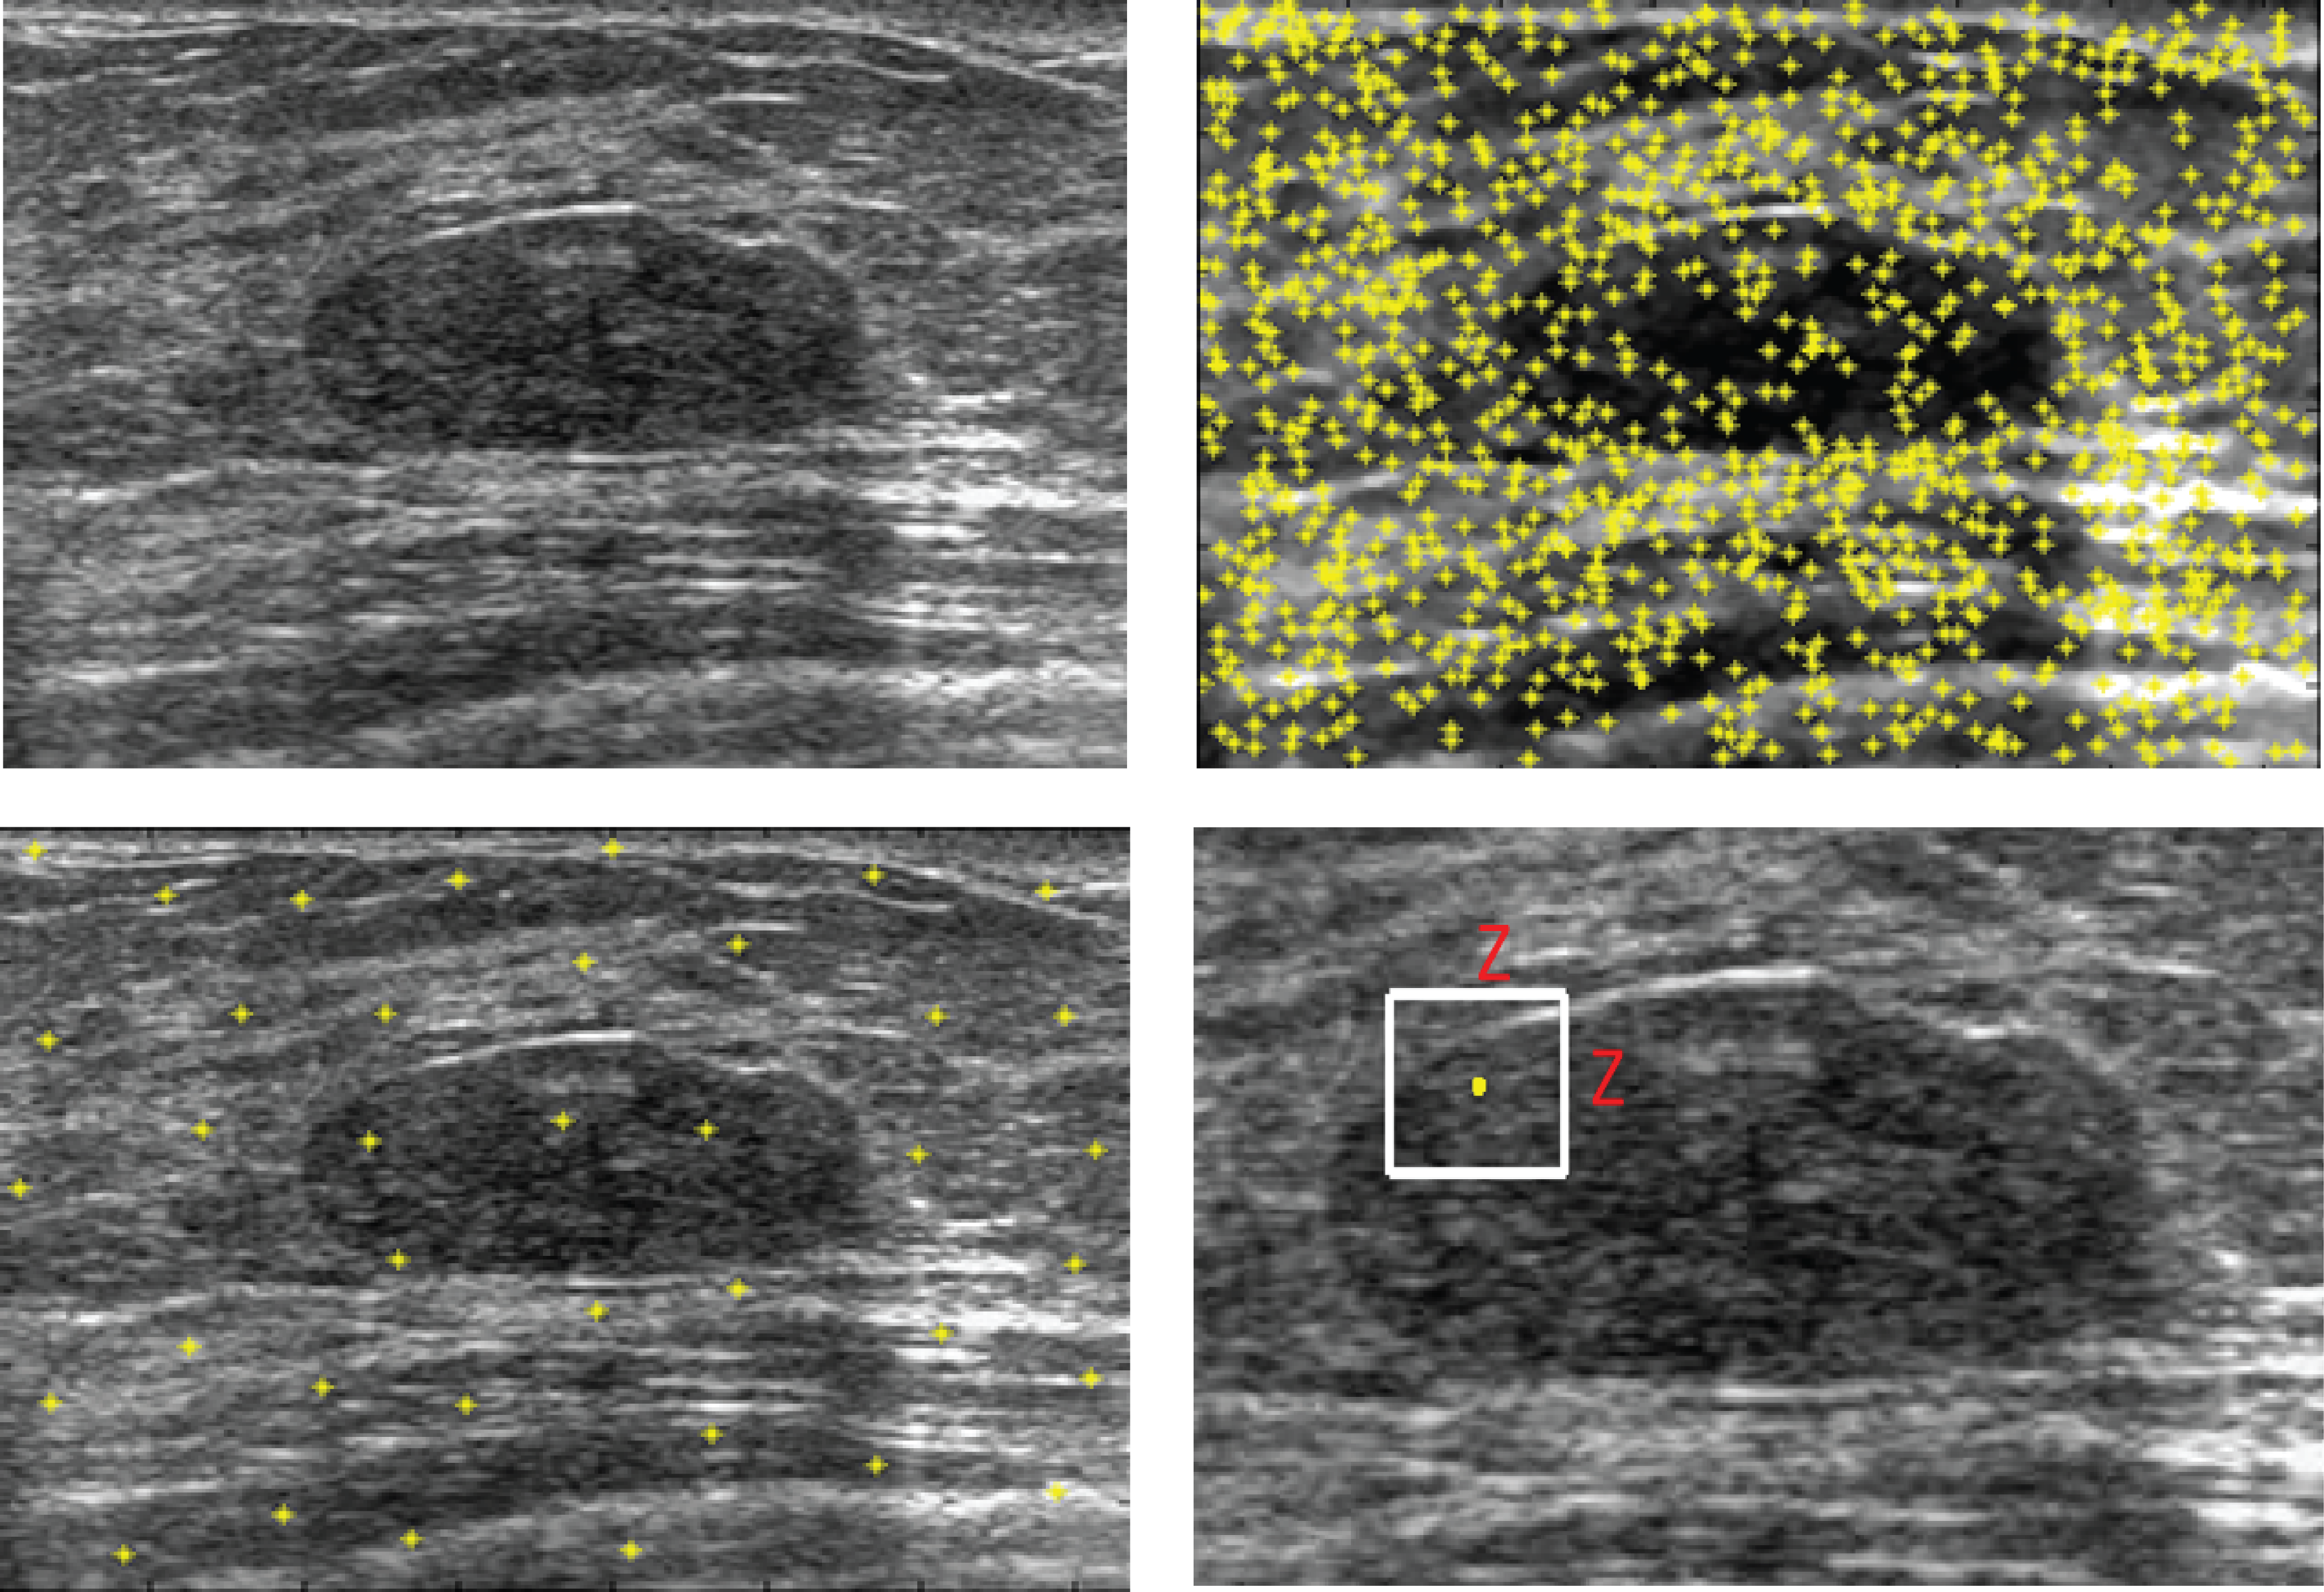

The target dataset was developed from 35 breast ultrasound scans that were segmented by an image-processing expert with extensive experience in breast lesion segmentation (the second author). The images, collected from the Web, are of different dimensions, ranging from to pixels (Figure 3, images resized for sake of illustration). These are the same images used to introduce EFIS originally [1].

Ultrasound images are generally difficult to segment, primarily due to the presence of speckle noise and low level of local contrast. It should be noted that the segmentation of ultrasound actually does require a complete processing chain, (including proper preprocessing and post-processing steps). However, the purpose of using these images was solely to demonstrate that the accuracy of the segmentation can be increased with the application of SC-EFIS.

The rectangle around each SIFT point to be used for feature calculation is determined based on different sizes of all available images (Algorithm 1). Following this step, the set of features that should be used for the available images is selected from a large number of features which are calculated for each image from the vicinity of the SIFT points located in the entire image (since there is no longer an ROI) (Fig. 1). This process starts with the determination of the number of SIFT points that should be used in the current image (algorithm 1). This step is identical to the procedure used in the EFIS training phase, as previously explained in section II, with three exceptions: the SIFT points are detected across the entire image (as opposed to selecting SIFT points inside an ROI as a subset of the image), the final number of SIFT seed points is not fixed, and the points returned are separated from each other by in each direction. For all seed points, features are extracted from a rectangle around each point, based on the discrete cosine transform () of , the gradient magnitude () of , the approximation coefficient matrix of (computed using the wavelet decomposition of ), and the SIFT descriptors . The following set of features is extracted (Algorithm 1):